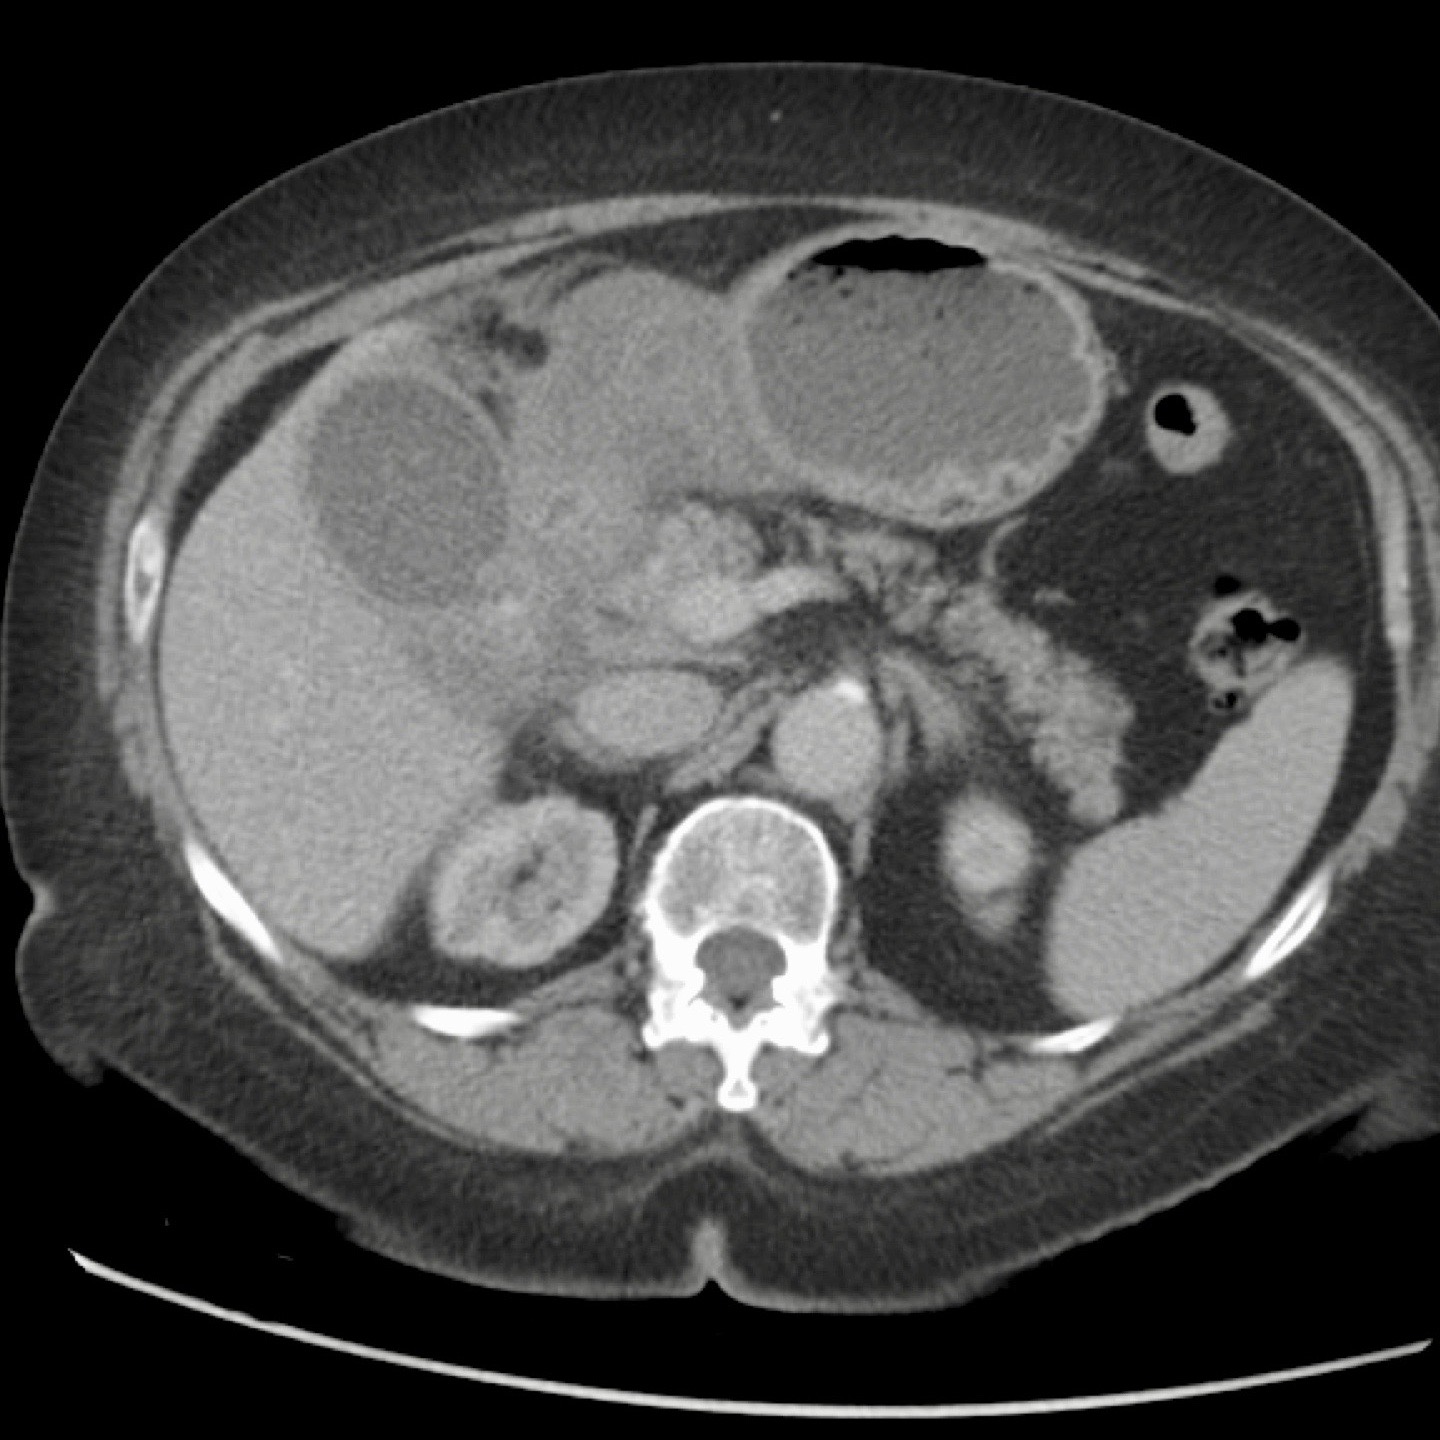

Bệnh nhân béo phì với đau thượng vị cấp tính.

Siêu âm cho thấy sỏi túi mật và dày thành, gợi ý viêm túi mật cấp.

CT thực hiện tiếp theo đã phát hiện bản chất thực sự của các triệu chứng: viêm tụy cấp do sỏi mật với dày thành túi mật thứ phát.